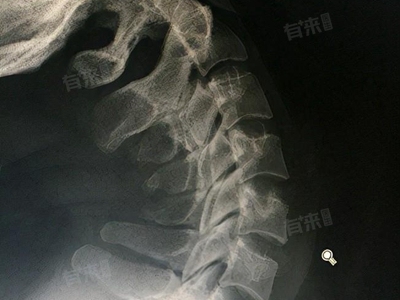

颈椎3、4、5、6、7膨出是一种较为常见的颈椎问题,可能会引起颈部疼痛、僵硬、上肢麻木等症状,有一些治疗方法,比如进行休息、药物治疗等。